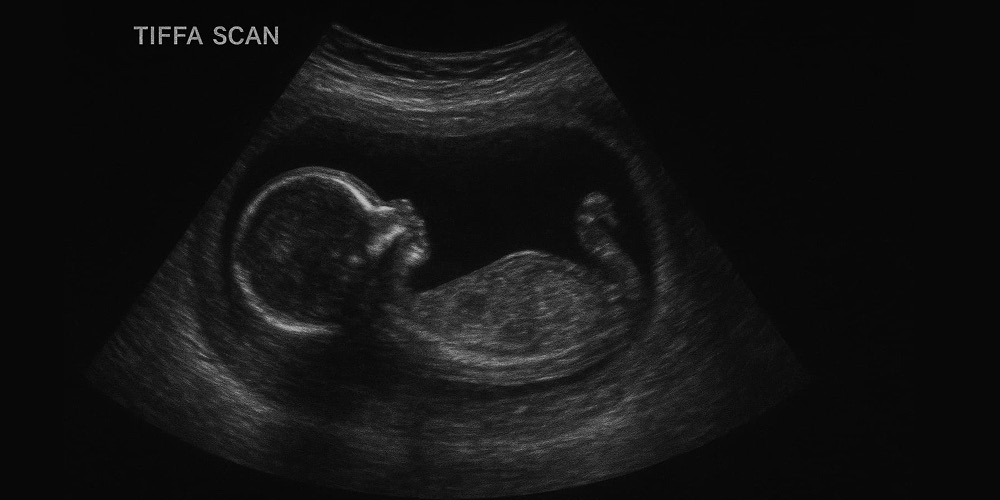

A TIFFA scan (Targeted Imaging for Fetal Anomalies) is a detailed ultrasound test which was done during pregnancy to check how your baby is growing and developing inside the mother’s stomach. It helps doctors see if all your baby’s organs through an ultrasound technique like the heart, brain, spine, kidneys, and limbs are forming normally or abnormally.

TIFFA Ultrasound is done with high-definition imaging technologies, where the sonographer uses some special gel on the abdomen of the mother and moves a transducer very smoothly over the abdomen to get clearer images of the baby inside the womb. Dr. Aravind's IVF gives that comfort level through the whole process and fully briefs mothers concerning what happens during every step.